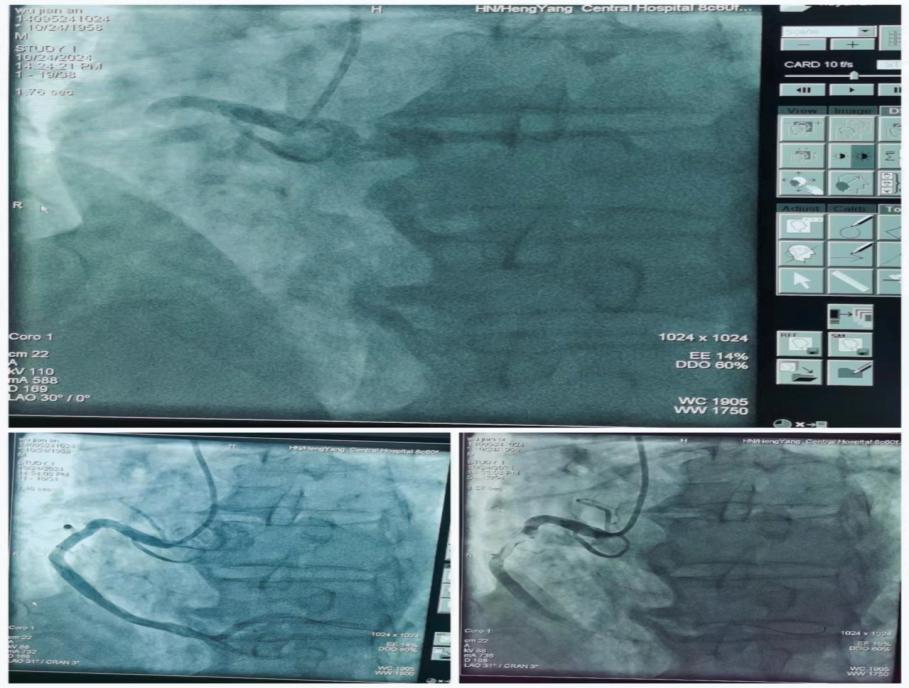

心內(nèi)科朱曉宇主任醫(yī)師急會(huì)診后,考慮Kounis綜合征-過敏性急性冠脈綜合征。與家屬溝通病情立即啟動(dòng)急性心梗急救流程,開通胸痛綠色通道送入導(dǎo)管室行急診PCI。急診冠狀動(dòng)脈造影顯示右冠第一轉(zhuǎn)折后完全閉塞并大量血栓影,賓建國副主任醫(yī)師帶領(lǐng)介入團(tuán)隊(duì)行急診右冠內(nèi)血栓抽吸+PTCA+支架植入術(shù),手術(shù)時(shí)間約40分鐘,術(shù)后病人安返心內(nèi)科病房。

圖片22.jpg

圖片23.jpg